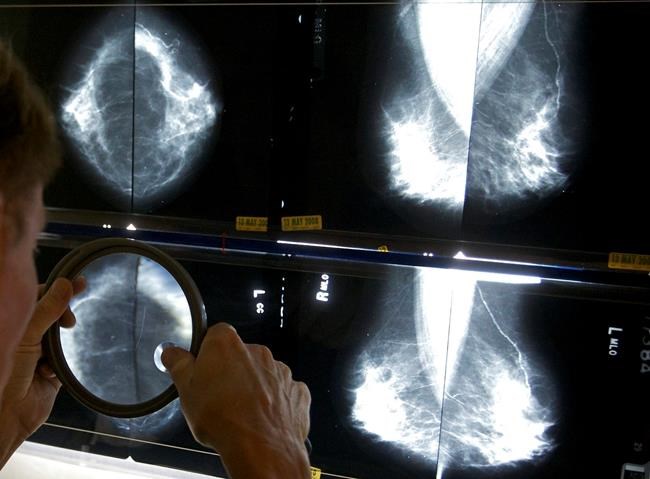

WASHINGTON – All U.S. women getting mammograms would receive information about breast density, which can sometimes make cancer harder to spot, under a government proposal released Wednesday.

More than half of women over age 40 have dense breasts, with less fatty tissue and more connective and glandular tissue. That tissue appears white on X-rays, the same colour as growths in the breast, making mammograms harder to read. Dense breast tissue is one of the factors that can increase a woman’s chances of developing cancer.

Under the FDA’s proposal, all women would receive a short summary about their breast density. For those with dense breasts, the letter would note that their tissue “makes it harder to find breast cancer,” and could require additional testing. The letter would also recommend that they speak with a doctor about their “individual situation.”

Professional guidelines don’t specify next steps for women identified with dense breasts, but some physicians may recommend additional forms of scanning, including ultrasound or MRI.

Mammogram reports to doctors have long included information about density. But it wasn’t routinely shared with women until some cancer survivors began pushing for disclosure laws. Congress gave the FDA authority to regulate standards for mammograms in 1992 and recently directed the agency to develop standard summary language.